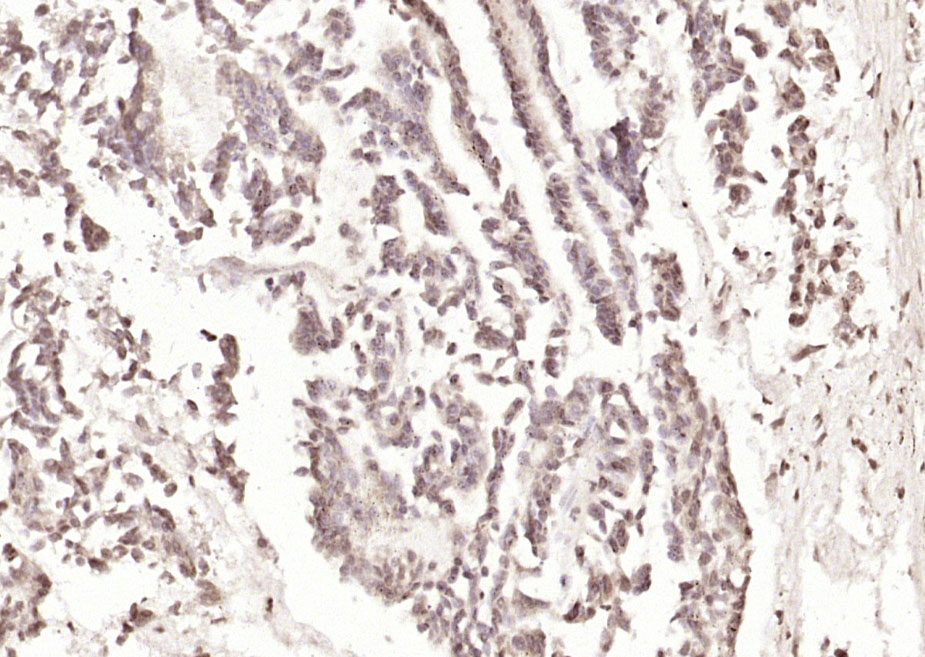

產(chǎn)品圖片

Paraformaldehyde-fixed, paraffin embedded (human gastric carcinoma); Antigen retrieval by boiling in sodium citrate buffer (pH6.0) for 15min; Block endogenous peroxidase by 3% hydrogen peroxide for 20 minutes; Blocking buffer (normal goat serum) at 37°C for 30min; Antibody incubation with (ST5) Polyclonal Antibody, Unconjugated (bs-6112R) at 1:200 overnight at 4°C, followed by operating according to SP Kit(Rabbit) (sp-0023) instructionsand DAB staining.